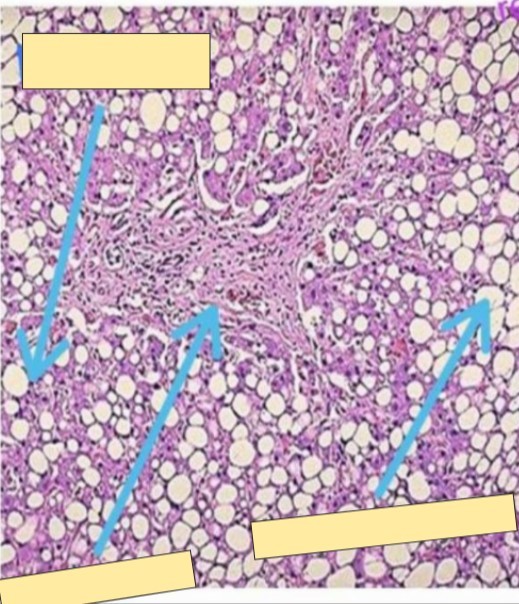

The _______ are distended by _______ which were occupied by _____ that had dissolved in ______during the preparation of the _____ section.

hepatocytes

cytoplasmic vacuoles

Fat

Xyol + alcohol

paraffin

The _______ of some hepatocytes are _______ by the vacuole (accumulated fat) to one side against the cell membrane giving the cell a _______ appearance.

A

Nuclei

flattened

Signet ring

Diagnosis?

Steatosis

liver steatosis